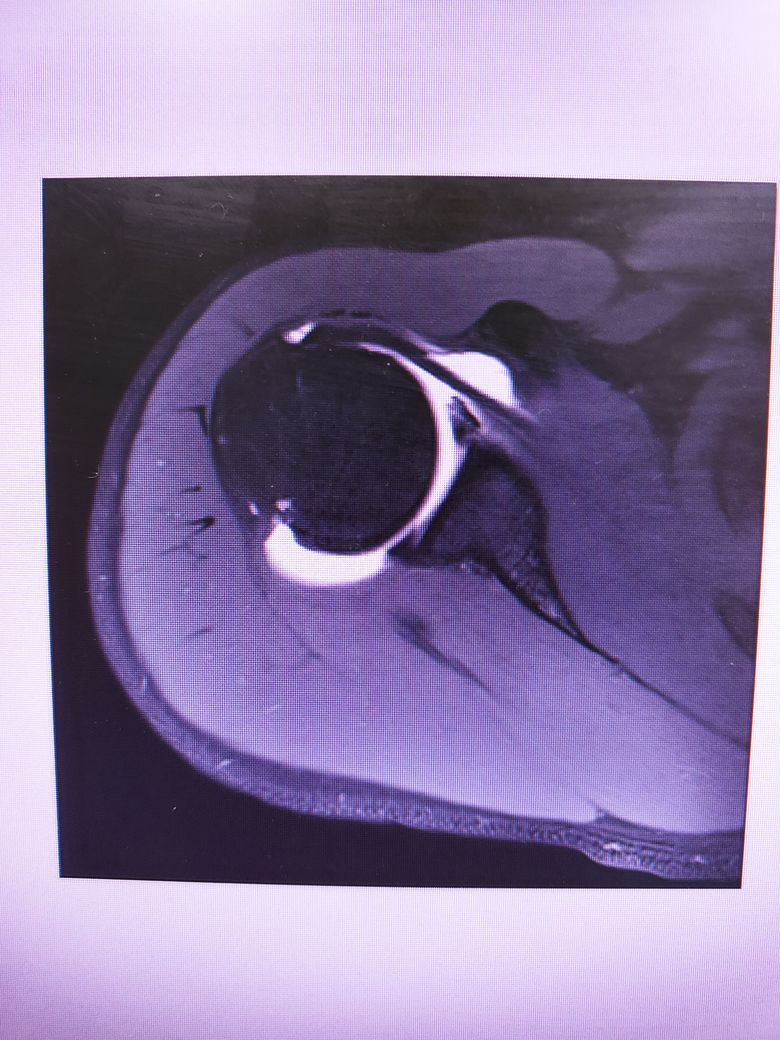

팔이 잡아당겨지는 사고 이후 통증이 지속되어

조영제 투입 후 mri 촬영을 하였습니다.

진단명은 상부관절와순파열(슬랩)이며

슬랩이 맞나요? 맞다면 파열 진행 정도는 어느정도인지..